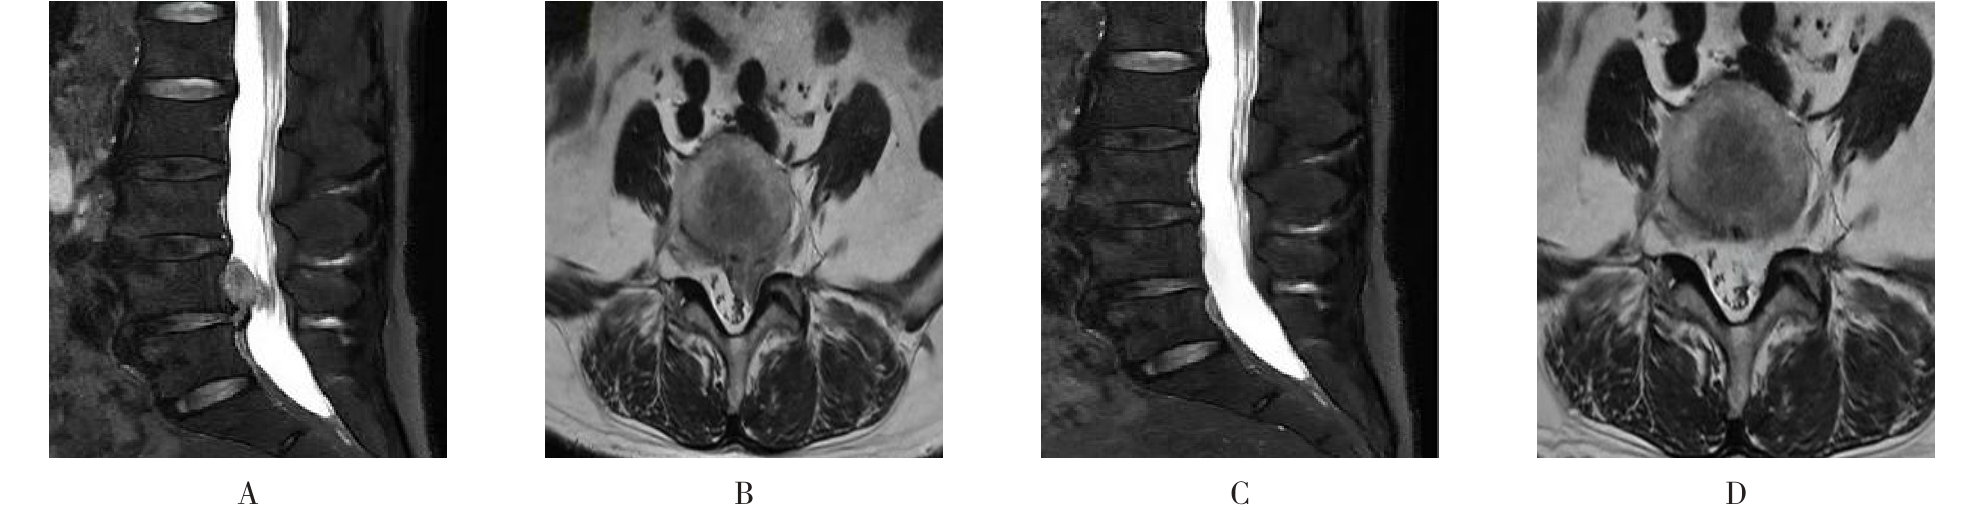

• 不同入路脊柱内镜手术治疗L4/5节段脱垂型腰椎间盘突出症的疗效比较

摘要:目的 观察经椎间孔入路内镜下腰椎间盘切除术(TELD)和经椎板间入路内镜下腰椎间盘摘除术(IELD)治疗L4/5节段脱垂型腰椎间盘突出症(LDH)的临床疗效。方法 回顾性分析2020年11月-2022年11月该院采用脊柱内镜手术治疗的75例L4/5节段脱垂型LDH患者的临床资料。根据手术入路的不同,将患者分为TELD组(53例)和IELD组(22例)。比较两组患者的手术情况和术后疗效。结果 与TELD组比较,IELD组的手术时间明显缩短,术中透视次数明显减少,差异均有统计学意义(P < 0.05);两组患者住院时间和并发症发生率比较,差异均无统计学意义(P > 0.05)。所有患者术后均获得12~19个月的随访。两组患者末次随访时的视觉模拟评分法(VAS)评分和Oswestry功能障碍指数(ODI)明显低于术前,且IELD组明显低于TELD组,差异均有统计学意义(P < 0.05)。按照突出物和神经根的不同位置进一步分析,两组肩上型患者(TELD组10例,IELD组6例)末次随访时的VAS评分和ODI明显低于术前,且IELD组末次随访时的VAS评分明显低于TELD组,差异均有统计学意义(P < 0.05);两组腋下型患者(TELD组8例,IELD组16例)末次随访时的VAS评分和ODI明显低于术前,且IELD组明显低于TELD组,差异均有统计学意义(P < 0.05);35例肩前型患者经TELD术后,末次随访时的VAS评分和ODI明显低于术前,差异有统计学意义(P < 0.05)。按照突出物的不同Lee分区进一步分析,两组Lee Ⅲ区患者(TELD组44例,IELD组10例)末次随访时的VAS评分和ODI明显低于术前,且IELD组的ODI明显低于TELD组,差异均有统计学意义(P < 0.05);两组Lee Ⅳ区患者(TELD组9例,IELD组12例)末次随访时的VAS评分和ODI明显低于术前,且IELD组明显低于TELD组,差异均有统计学意义(P < 0.05)。结论 采用TELD和IELD治疗L4/5节段脱垂型LDH,均可获得较满意的减压效果,但IELD的手术时间相对较短,X线透视次数较少,且对肩上型、腋下型、Lee Ⅲ区和Lee Ⅳ区的减压效果更有优势。